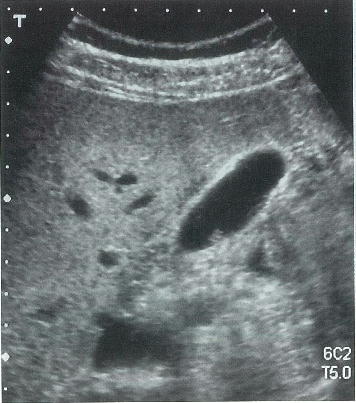

35歳の男性。人間ドックの腹部超音波検査で異常を指摘され来院した。身長 172cm,体重 80kg。腹部に異常を認めない。血液所見:赤血球 450万,Hb 14.8g/dl,白血球 6800。血清生化学所見:AST 24IU/l,ALT 53IU/l,γ-GTP 84IU/dl(基準 8~50)。腹部超音波写真を別に示す。検査中,体位による病変の移動はみられなかった。

診断 胆嚢ポリープ(コレステロールポリープ),脂肪肝